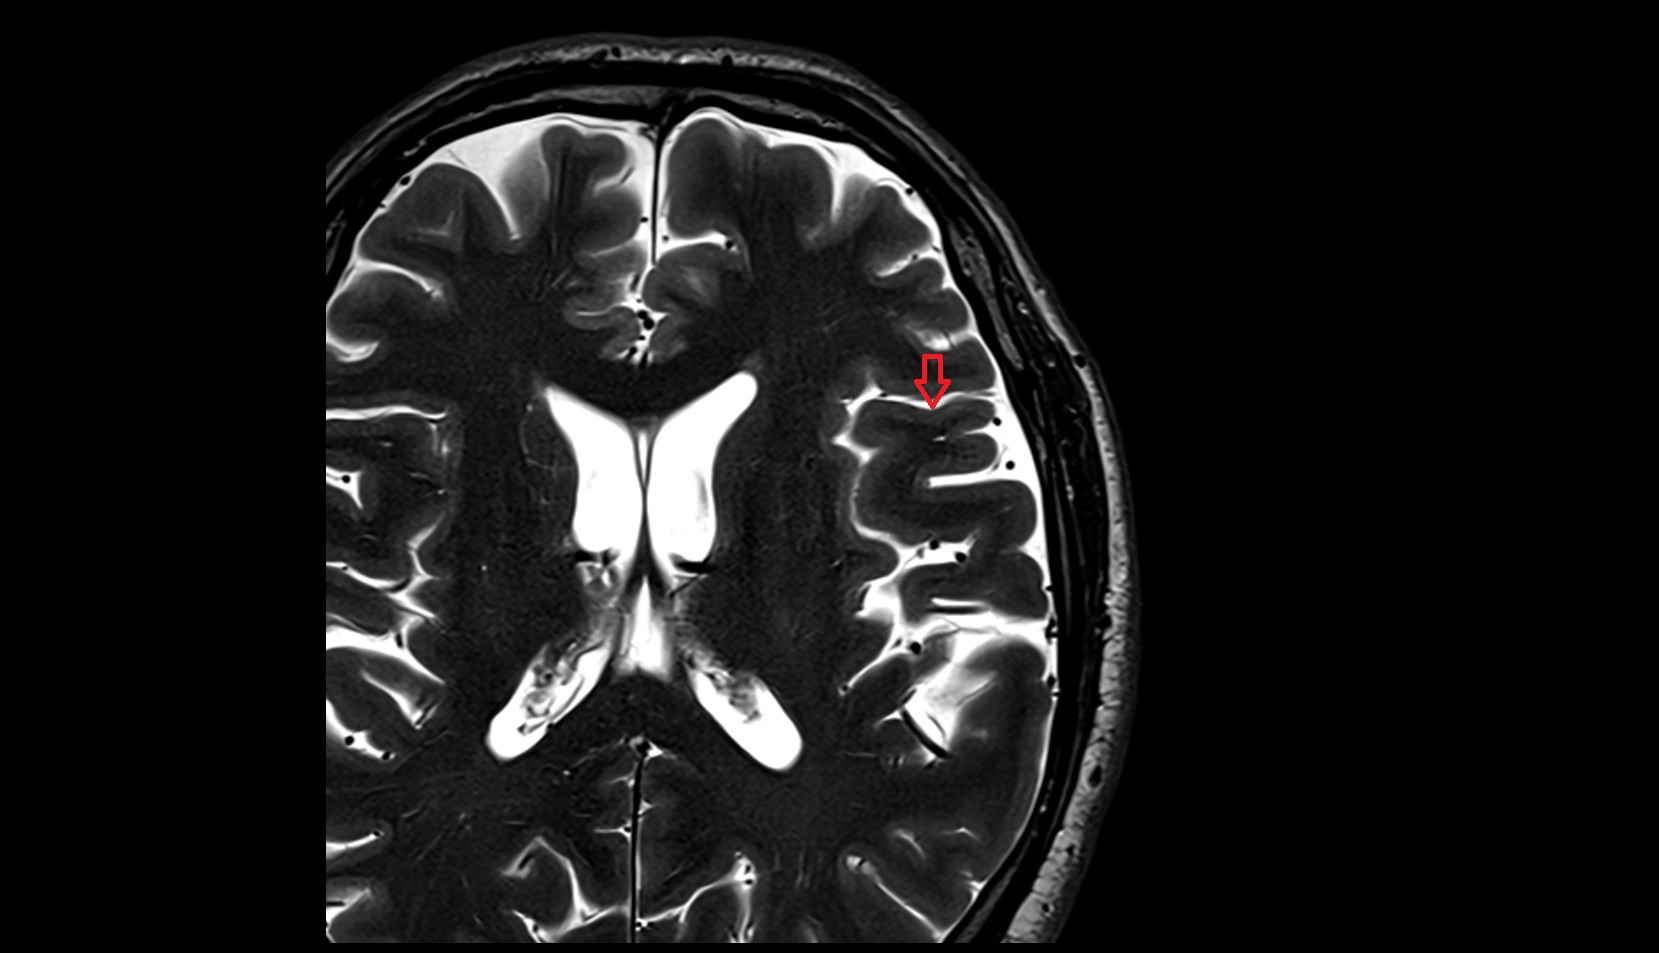

- Central sulcus